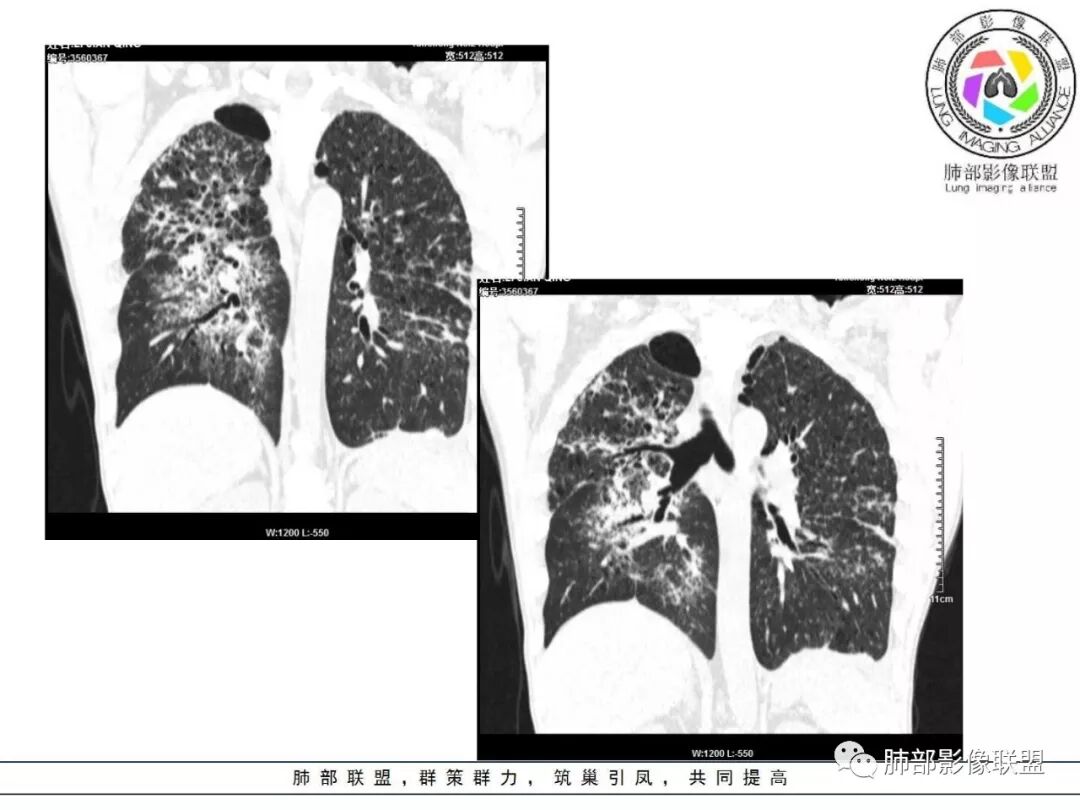

胸部CT:两肺弥漫病灶,磨玻璃影,少许实变,部分累及胸膜,磨玻璃区可见囊?少许胸腔积液,两肺可见结节,支气管血管束增粗,小叶间隔增厚,支气管走形有扭曲扩张,可见纤维化。气肿、大泡。考虑:感染性病变,PCP?查下HIV,CD4,G等。鉴别结核、结缔组织病肺浸润。

中年男性,亚急性病程,发热黄痰,c反应高;CT:分布胸膜下,支气管血管束周围,中上肺为主;磨玻璃、牵拉支扩,气管支气管粗,纵隔窗肺门淋巴结密度高;考虑:1)OP伴感染;2)巨气管支气管症;鉴别其他引起淋巴系统增殖性疾病如TB、NTM、淋巴瘤,当然有钙化,似乎淋巴瘤不太支持,需要进一步完善检查

胸部CT:两肺弥漫病灶,中央间质分布为主,部分位于胸膜及叶间裂旁,磨玻璃影,斑片影,部分实性结节,肺气囊,支气管血管束增粗,小叶间隔增厚,叶间裂不均匀增厚,支气管走形有扭曲扩张,可见纤维化、气肿、大泡。考虑:LIP加MALT。鉴别PLCH、PCP、结核、结缔组织病肺浸润。

中老年男性,双肺弥漫性病变,呈网状、斑片及大片状,实变影及磨玻璃影相间,部分病灶区支气管扩张,并见多发小囊状或蜂窝状透亮影,中央间质增厚,气管前单发小淋巴结。考虑淋巴细胞增生性病变?粘膜相关性淋巴瘤(MALT)或淋巴细胞间质性肺炎(LIP)?鉴别机化性肺炎(OP)及结核(TB)。

两肺弥漫病灶,中央间质分布为主,部分位于胸膜及叶间裂旁,磨玻璃影,斑片影,部分实性结节,肺气囊,支气管血管束增粗,小叶间隔增厚,叶间裂不均匀增厚。考虑:间质性肺病,LIP,鉴别OP

两肺弥漫性病变,沿支气管血管束分布,部分细支气管轻度扩张,两上中肺为主,部分累及胸膜下,部分磨玻璃影,部分纤维化,肺气肿肺大疱背景,胸膜增厚,少量积液,病程一月余,crp高反复发热,两肺门区增大钙化淋巴结,间质性疾病,考虑淋巴增殖性病变为主,结核可能性大,待鉴别NTM,结节病,LIP,PCP纤维化

中老年男性,发热1月余,双肺弥漫性病变,多发网格、结节、斑片状实变影及磨玻璃影,胸膜下及中轴间质都受累,支气管血管束增粗、变形,支气管扩张,叶间裂及小叶间隔增厚,整体间质性改变明显,考虑结核?OP、LIP?进一步除外PCP、肿瘤、结节病等。

2. 肺气肿背景(小叶中心性肺气肿);双肺多发病灶整体沿血管支气管束及胸膜下分布,以上叶及下叶背段分布为主,有实变及GGO,边界清楚,有树芽,小叶间隔及中央间质增厚,叶间裂见到多发结节,部分支气管不规则牵拉扩张,提示病灶纤维化明显,结合临床病史,考虑病灶为间质性感染,肺门及纵隔内有钙化淋巴结,小叶间隔结节,考虑淋巴道增值性疾病可能,综合常规要怀疑间质性肺结核。